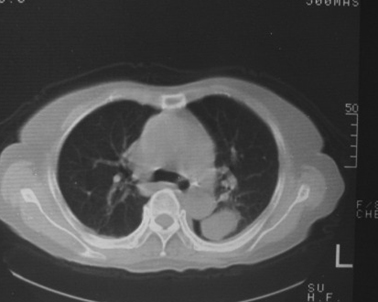

女,80岁,10天前胸片示双下肺感染,正规治疗后复查。体温不高,有脓痰,无臭味。

左肺下叶块影约为17hu!

左下肺片状及块状密度增高影,其内见液化密度影及充气支气管影.考虑炎性病灶,肺脓肿形成

左肺下叶大部实变,内可见含气支气管征。后部见长椭圆形低密度区,周围坏一薄壁。

考虑:左下肺炎症,包裹性胸腔积液。

支持:左肺下叶大部实变,内可见含气支气管征。后部见长椭圆形低密度区,周围环一薄壁,局部胸膜增厚。结合病史考虑:左下肺炎症,包裹性胸腔积液。